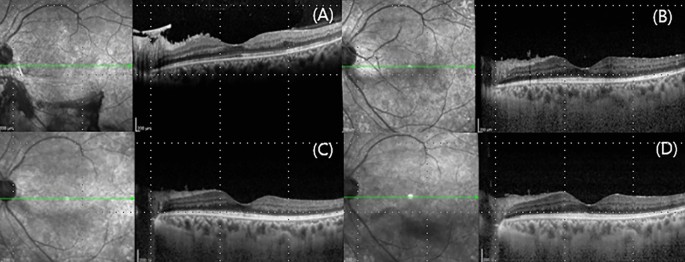

The first patient a 39-year-old female followed up for 6 years. She initially presented to the clinic with a left eye floater and best-corrected visual acuity of 1.0 and 0.63 in the right and left eyes, respectively. She said she had no history of diabetes mellitus. Fundus examination showed mild VH in left eye and new vessels in both eyes. FA revealed bilateral NVE and NVD. Her HbA1c level was 10.1%, for which she was referred to the endocrinology department. We performed PRP in both eyes. Six months thereafter, NVD progressed in her left eye. Repeat FA revealed severe NVD leakage without NVE, and additional laser treatment was performed in areas not adequately treated with PRP (Fig. 1). However, NVD was not reduced, and moderate VH occurred almost 2 months after the additional laser treatment. As a result, IVAI was performed, which led to improvements in VH and NVD. However, NVD reappeared over time (Fig. 2) and VH recurred 4.5 months after the initial IVAI. Therefore, the patient was monitored for NVD and IVAI was repeated at 4-month intervals. The patient underwent nine IVAIs over 52 months, and had no NVD regeneration or VH recurrence during 18 months after last treatment. (Fig. 3).

Change in the new vessel on the disc of case 1 before and after anti-vascular endothelial growth factor antibody injection (IVAI) treatment: (A) 1 month after the initial IVAI, (B) 2 months after the initial IVAI, (C) 3 months after the initial IVAI, and (D) 1 month after the second IVAI. NVD regressed immediately after IVAI, but progressed over time and was maximally engorged 4 months after IVAI.